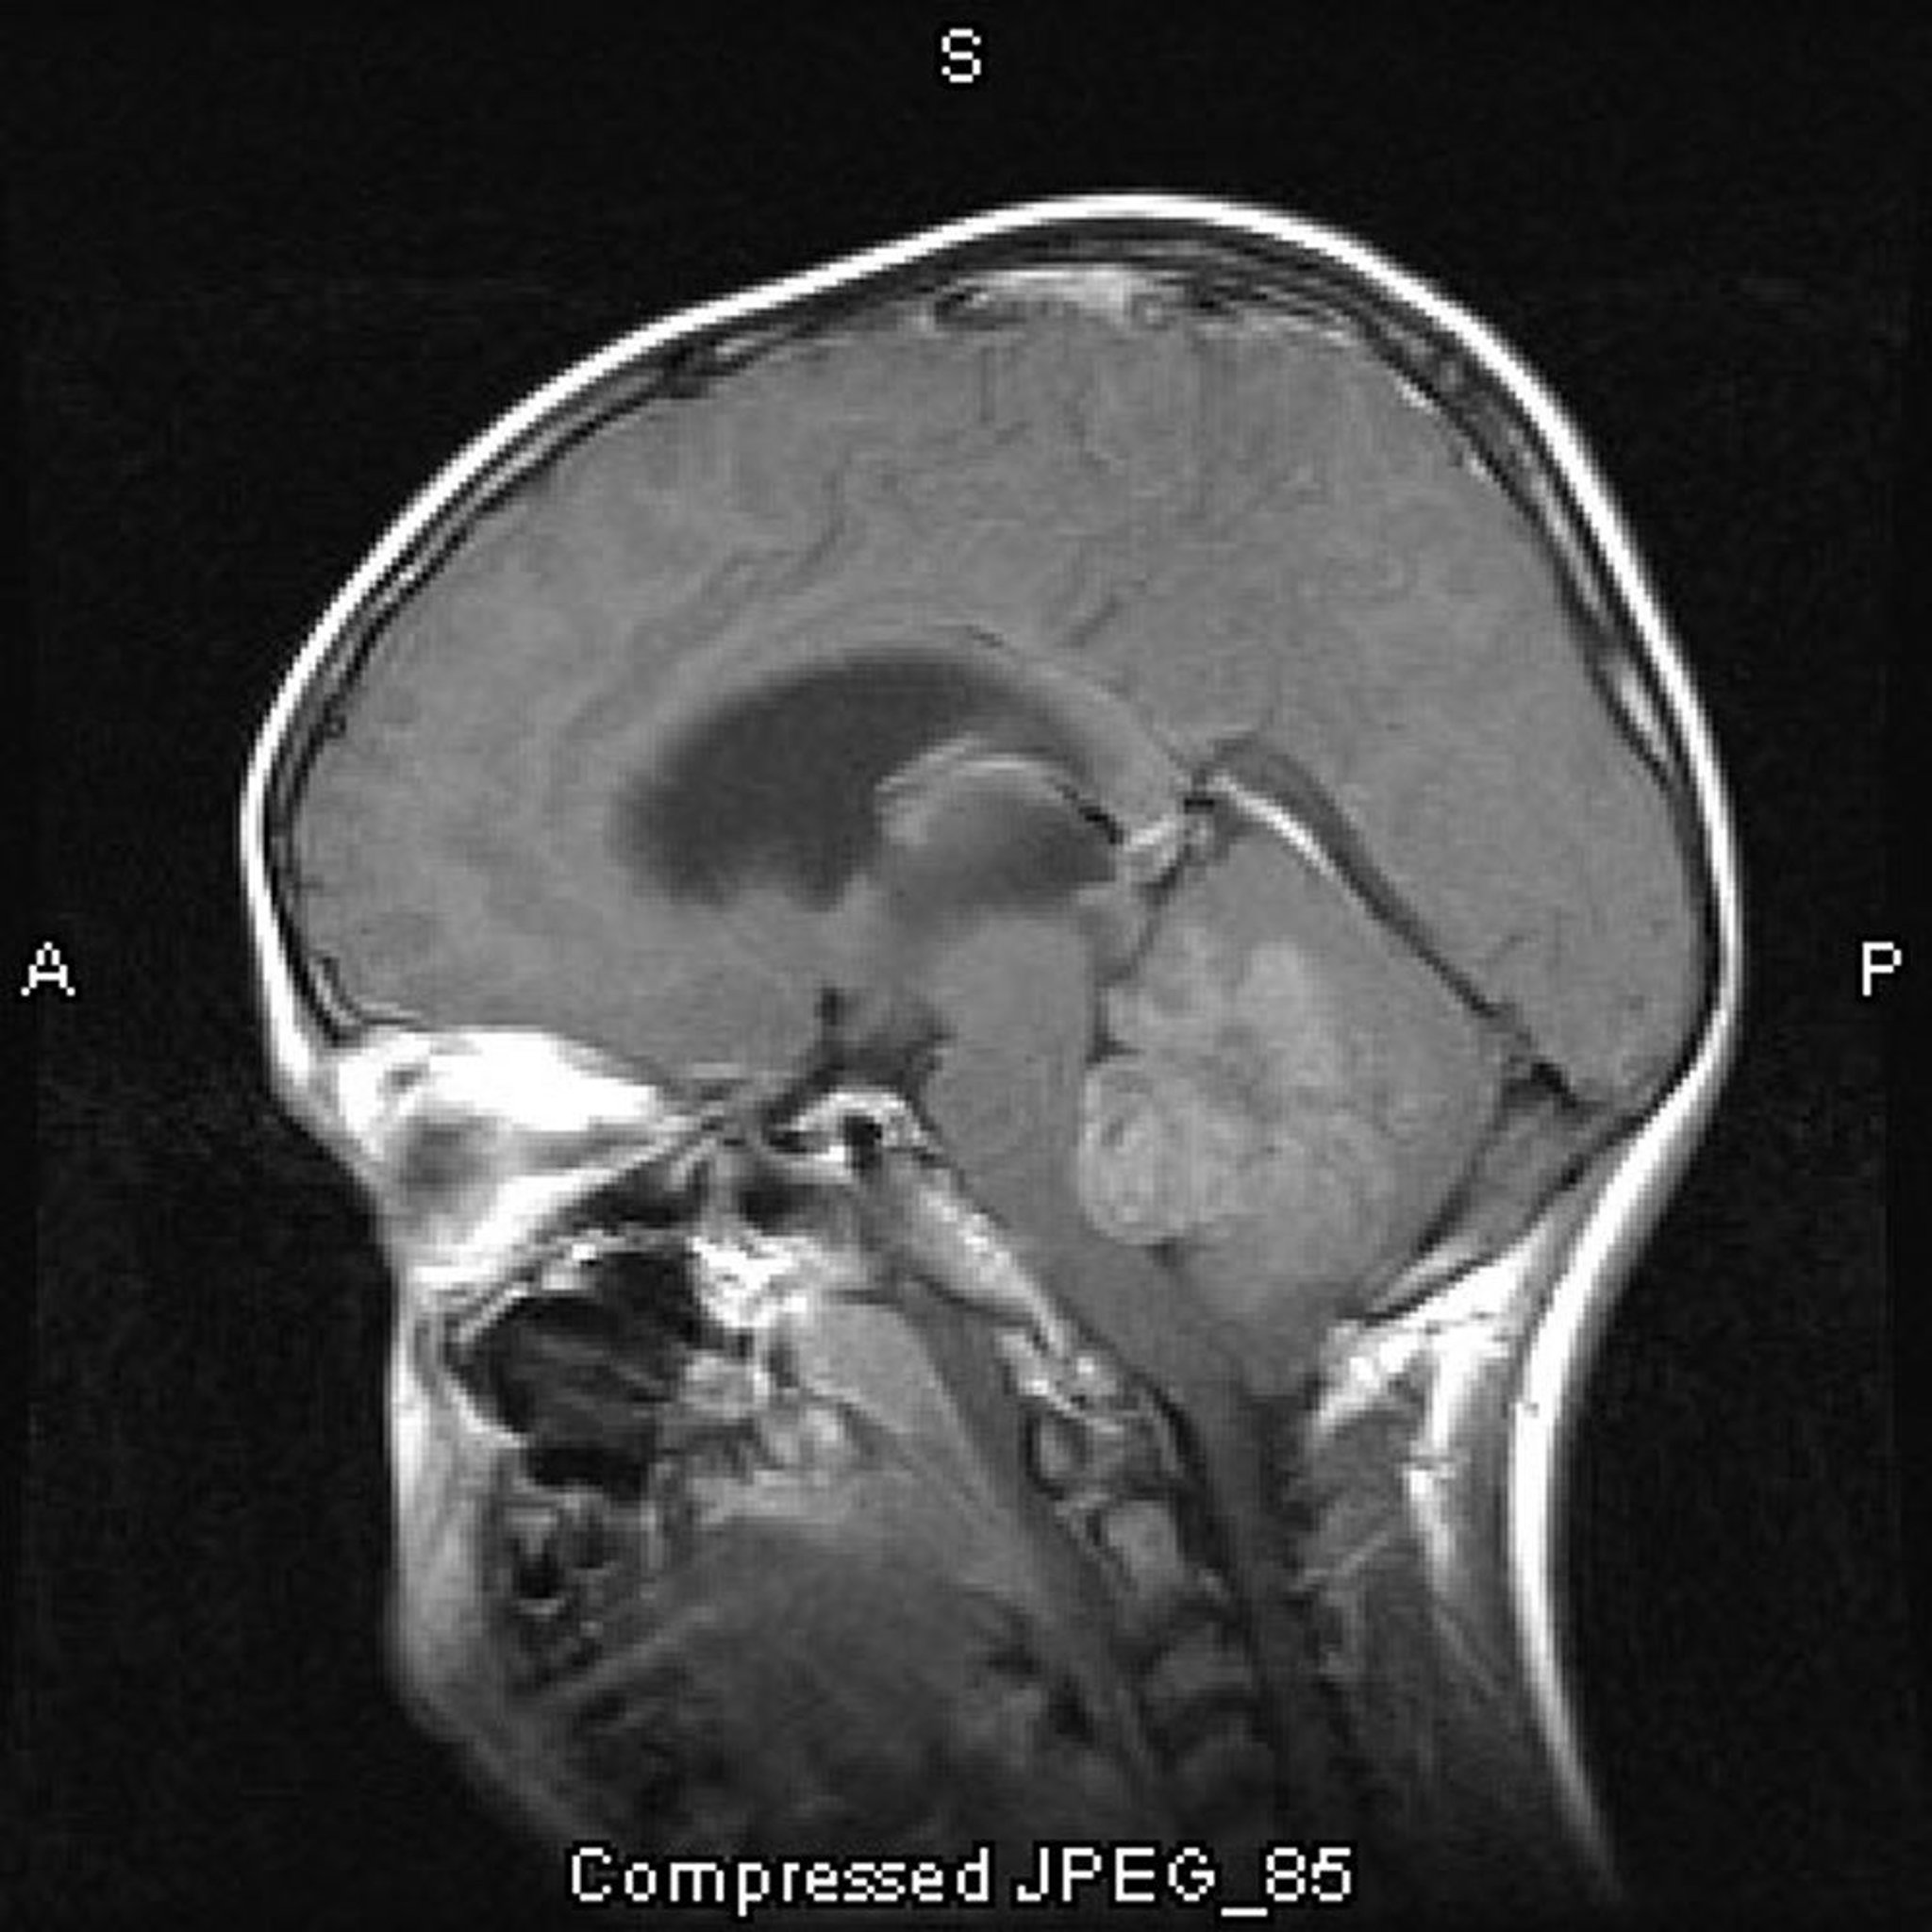

Meduloblastoma

Essa RM com contraste mostra um meduloblastoma crescendo na parte superior e obstruindo o 4º ventrículo.

Imagem cedida por cortesia de William R. Shapiro, MD.